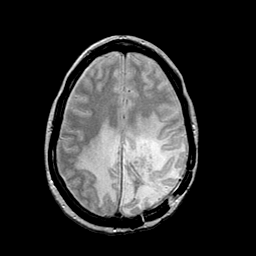

MR Study #2 -- Slice #36